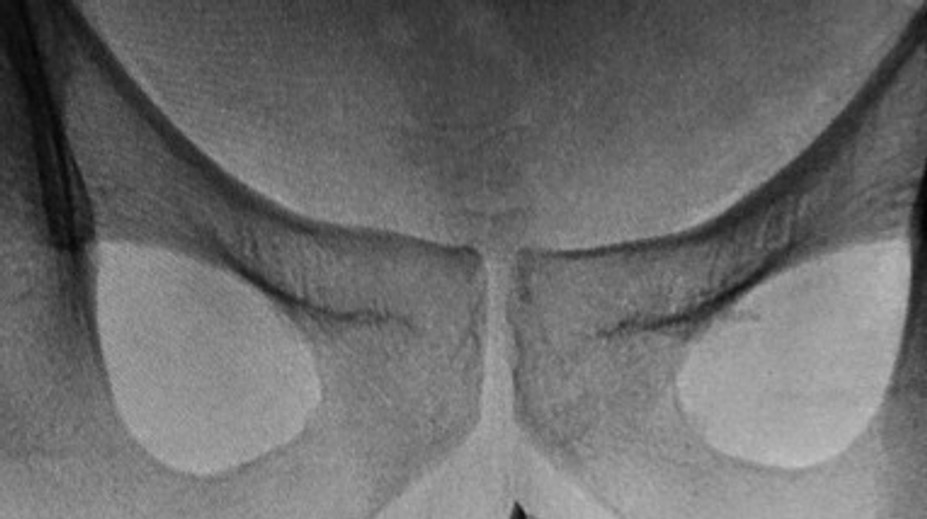

Mladík (22) mal štyri roky v penise netypický predmet. Necítil vraj žiadnu bolesť Róbert Ďurkáč 15. 10. 2019